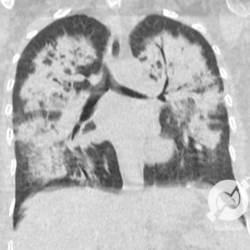

Lesões intersticiais reticulares difusas, aumento do volume cardíaco (Rx)/Opacidades em vidro fosco, espessamento septal e consolidações alveolares difusas, com predomínio peri-hilar bilateral. Edema agudo de pulmão.

Opacidades em vidro fosco difusas com espessamento liso de septos e moderado derrame pleural bilateral.

Opacidades em vidro fosco difusas com espessamento liso de septos e pequeno derrame pleural bilateral.

Opacidades em vidro fosco, espessamento septal liso, proeminência de estruturas venosas e derrame pleural bilateral.